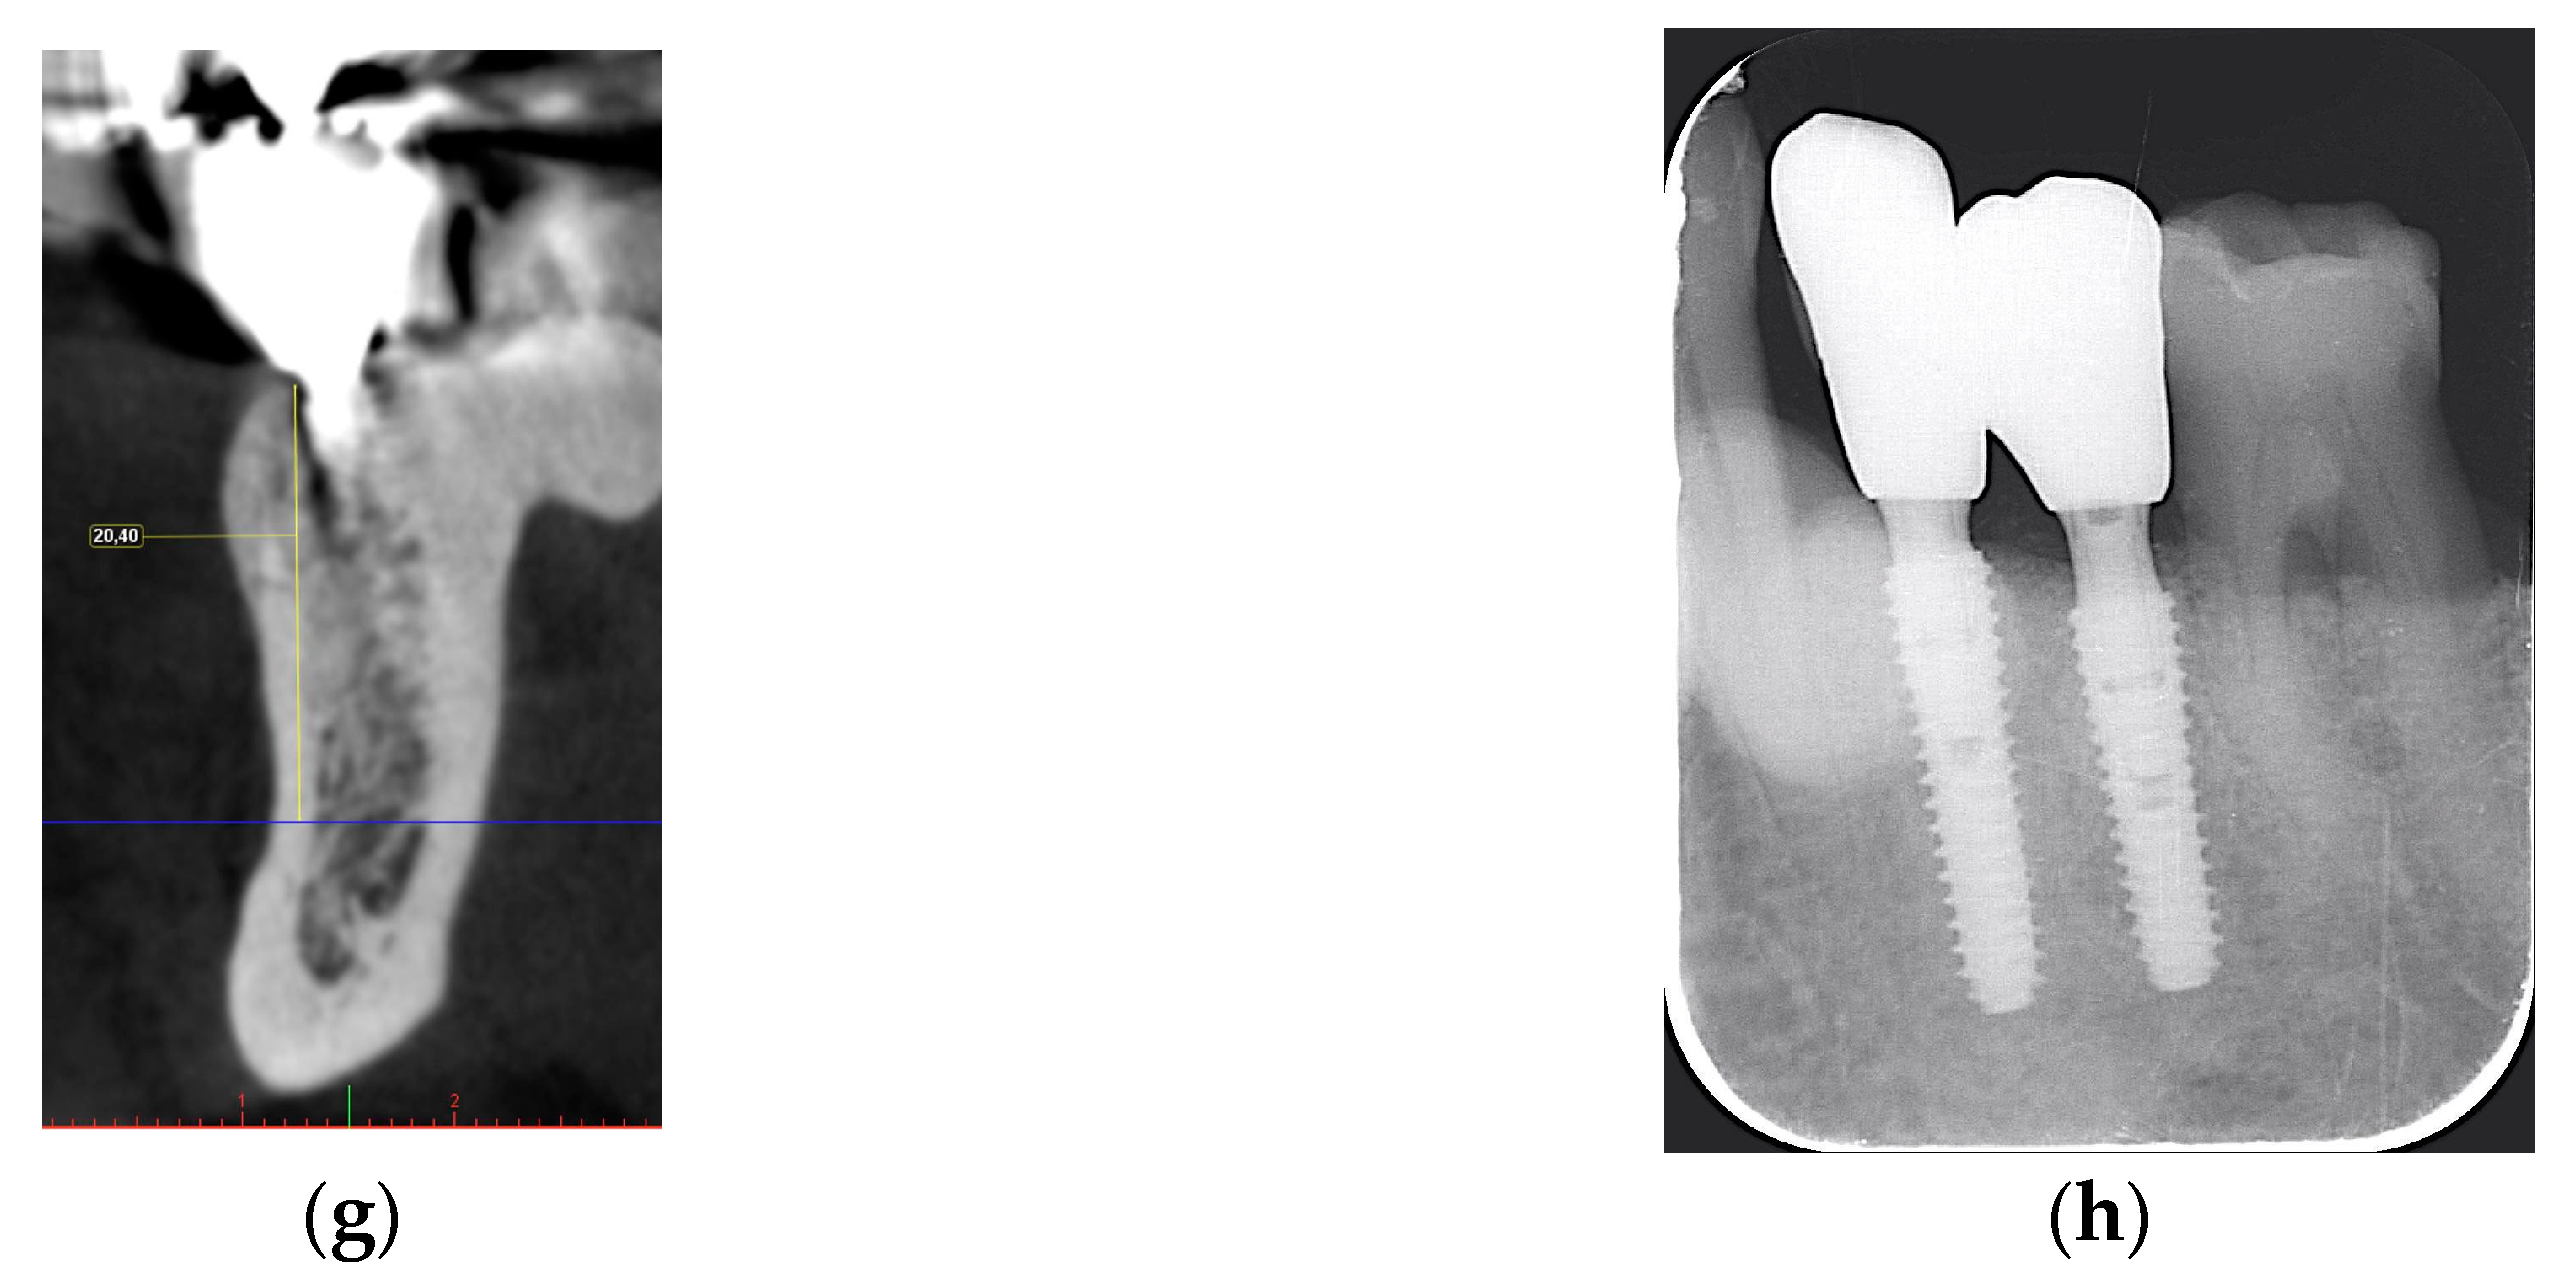

2.2.1. Horizontal and Vertical GBR Using F.I.R.S.T.

2.2.2. Immediate Implant Placement Using F.I.R.S.T.

2.2.3. ARP and Delayed Implant Placement Using F.I.R.S.T.

- Foti, V.; Rossi, R. Fibrinogen-induced regeneration sealing technique (first) an improvement and modification of traditional gbr: A report of two cases. Mod. Res. Dent. 2020, 5, 476–485. [Google Scholar]

- Foti, V.; Savio, D.; Rossi, R. One-time cortical lamina: A new technique for horizontal ridge augmentation. A Case Ser. Br. J. Healthc. Med. Res. 2021, 8, 22–30. [Google Scholar] [CrossRef]

- Foti, V. Fibrinogen-induced regeneration sealing technique (f.I.R.S.T.). In Building Better Bone: A Comprehensive Guide to gbr Techniques; Rossi, R., Ed.; Quintessence Publishing: Batavia, IL, USA, 2024; pp. 210–227. [Google Scholar]

- Faro, L.L.; Strappa, E.M.; Carù, F.G.; Nanni, M.; Invernizzi, M.; Testori, T. Rigenerazione ossea guidata con tecnica first (fibrin-induced regeneration sealing technique). Case report con evidenze istologiche. Quintessenza Internazionale Riv. Di Odontoiatr. 2023, 37, 10–21. [Google Scholar]